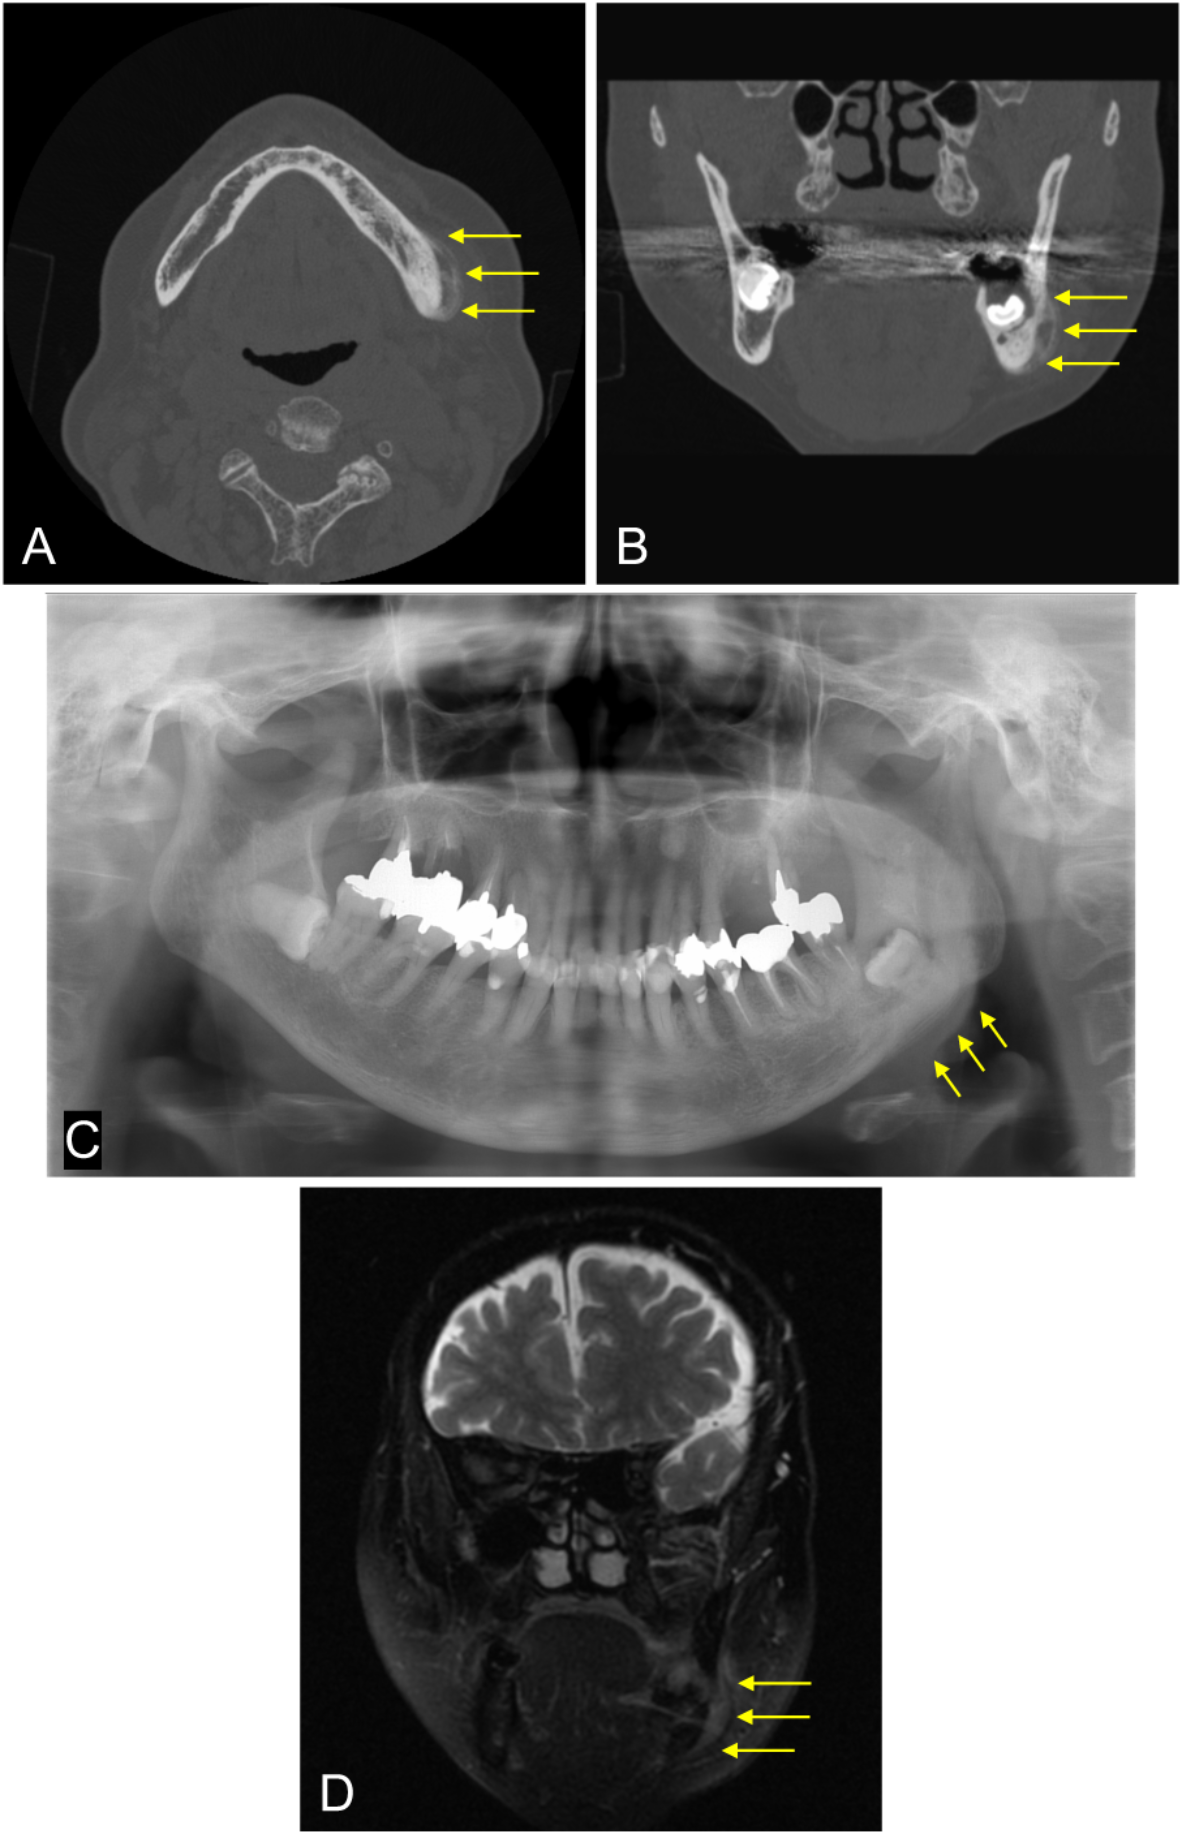

Fig. 4

Case with periosteal reaction. A 70-year-old female experienced discomfort in the lower left molar region and sought care at a dental clinic. Initially, she was informed about the impacted lower left third molar but was left untreated. Later, swelling in the area developed, leading to a referral to our hospital. She was diagnosed with bacterial OM because of exclusion from the ORN or MRONJ criteria. (A, B) The CT images (bone mode) showing an area of increased CT values continuous with the outer cortical bone (arrows). (C) Panoramic X-ray image revealing increased radiopacity (new bone formation) along the lower border of the mandible (arrows). (D) T2-weighted fat-suppressed MR image displaying a high signal intensity area continuous with the outer cortical bone (arrows).